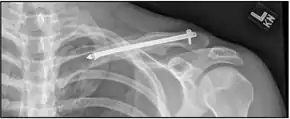

| X-ray of a left clavicle fracture | |

The basic method to check for a clavicle fracture is by an X-ray of the clavicle to determine the fracture type and extent of injury. In former times, X-rays were taken of both clavicle bones for comparison purposes. Due to the curved shape in a tilted plane X-rays are typically oriented with ~15° upwards facing tilt from the front. In more severe cases, a computerized tomography (CT) or magnetic resonance imaging (MRI) scan is taken. However, the standard method of diagnosis through ultrasound imaging performed in the emergency room may be equally accurate in children.[6]

A discontinuity in the bone shape often results from a clavicular fracture, visible through the skin, if not treated with surgery. Surgical procedures often call for open reduction internal [plate] fixation where an anatomically shaped titanium or steel plate is affixed along the superior aspect of the bone by several screws. In some cases, the plate is removed after healing due to discomfort, to avoid tissue aggravation, osteolysis or subacromial impingement. This is especially important with a special type of fixation plate called hook plate.[15] With anatomical plates plate removal is considered an elective procedure that is rarely necessary. An alternative to plate fixation is elastic TEN intramedullary nailing. These devices are implanted within the clavicle's canal to support the bone from the inside. Typical surgical complications are infection, neurological symptoms distal the incision (sometimes to the extremity), and nonunion of the bone (failure of the bone to properly fuse together).